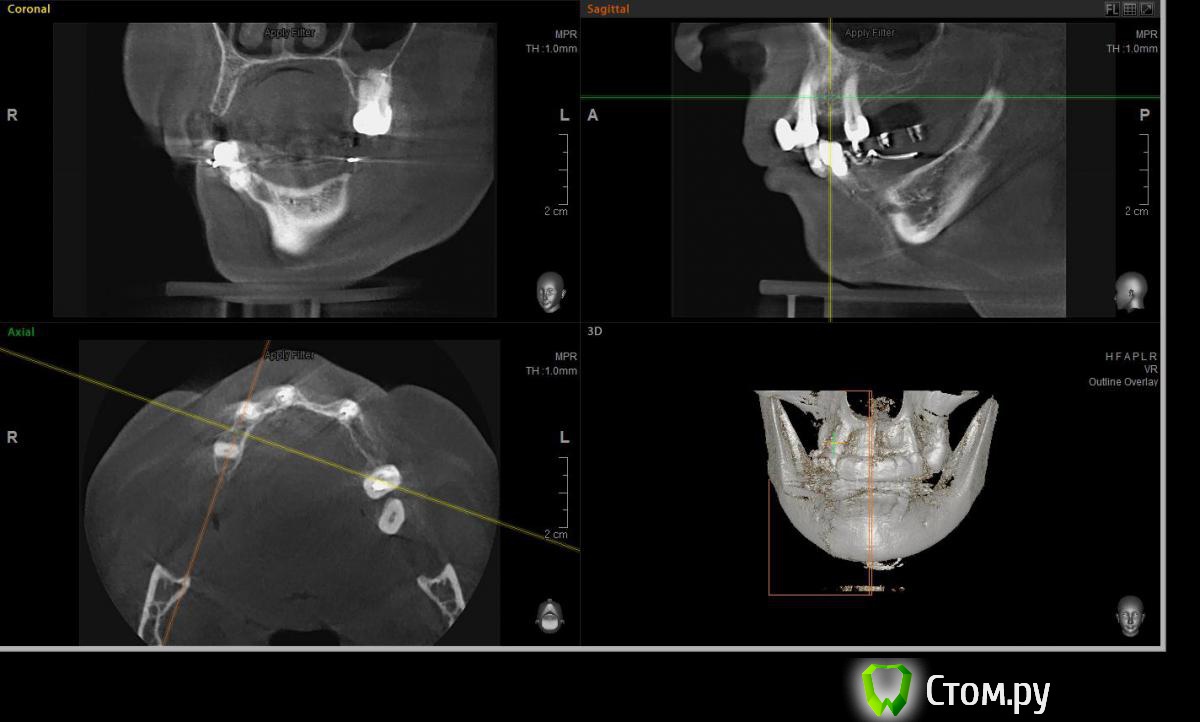

Евгений Ходыкин Опубликовано 23 июля, 2014 Поделиться Опубликовано 23 июля, 2014 Решили с пациенткой пока начать с в.ч. В планах имплантация в область отсутствующих 1.6, 1.4, 1.2, 2.1, 2.2, 2.4, 2.5. С 1.6 самому более менее все понятно, мануальных навыков хватит) Прошу помощи коллег относительно остальных областей. Фронт особливо печален... Забегая наперед скажу, что блоки еще не делал. Ауто точно пока брать не планирую, ибо нет даже теоретических навыков. Хочу начать все-таки с аллоблоков. У кого какие будут мнения, заранее спасибо) Ссылка на комментарий

Sahan Опубликовано 23 июля, 2014 Поделиться Опубликовано 23 июля, 2014 Здесь все показания для ауто блоков во фронте. В боковых отделах либо расщепление , либо сетка с одномоментной имплантацией. Алло материалом во фронте не справиться , слишком большой обьем требуется вырастить. 1 Ссылка на комментарий

Rafael_Gogyan Опубликовано 24 июля, 2014 Поделиться Опубликовано 24 июля, 2014 (изменено) фронт блоклибо сосиску (минимум 50% ауто) с одномоментной имплантациейв боковых отделах особых проблем не вижу. имплантация с НТР в обеих случаях + ССТ на ножке с нёба Изменено 24 июля, 2014 пользователем Rafael_Gogyan Ссылка на комментарий